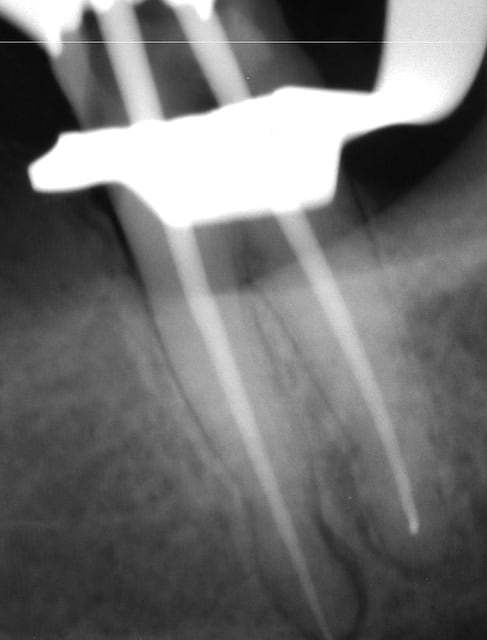

Je remets celles que j'ai faites hier on sait jamais si quelqu'un est intéressé (mais je venais sur ce post surtout pour avis dans la démarche.

Je pense me faire un "book" en plus (où je mettrais tout, réussi comme raté.)

Toutes mes endos d'hier (elles sont dans un autre sujet aussi)

--

www.dentaltradegroup.com

Endo 1  1   preop f9tl26 - Eugenol

Endo 1  2  fin oyre3e - Eugenol

Endo 2 g96boc - Eugenol

Endo 8 l0w3t1 - Eugenol